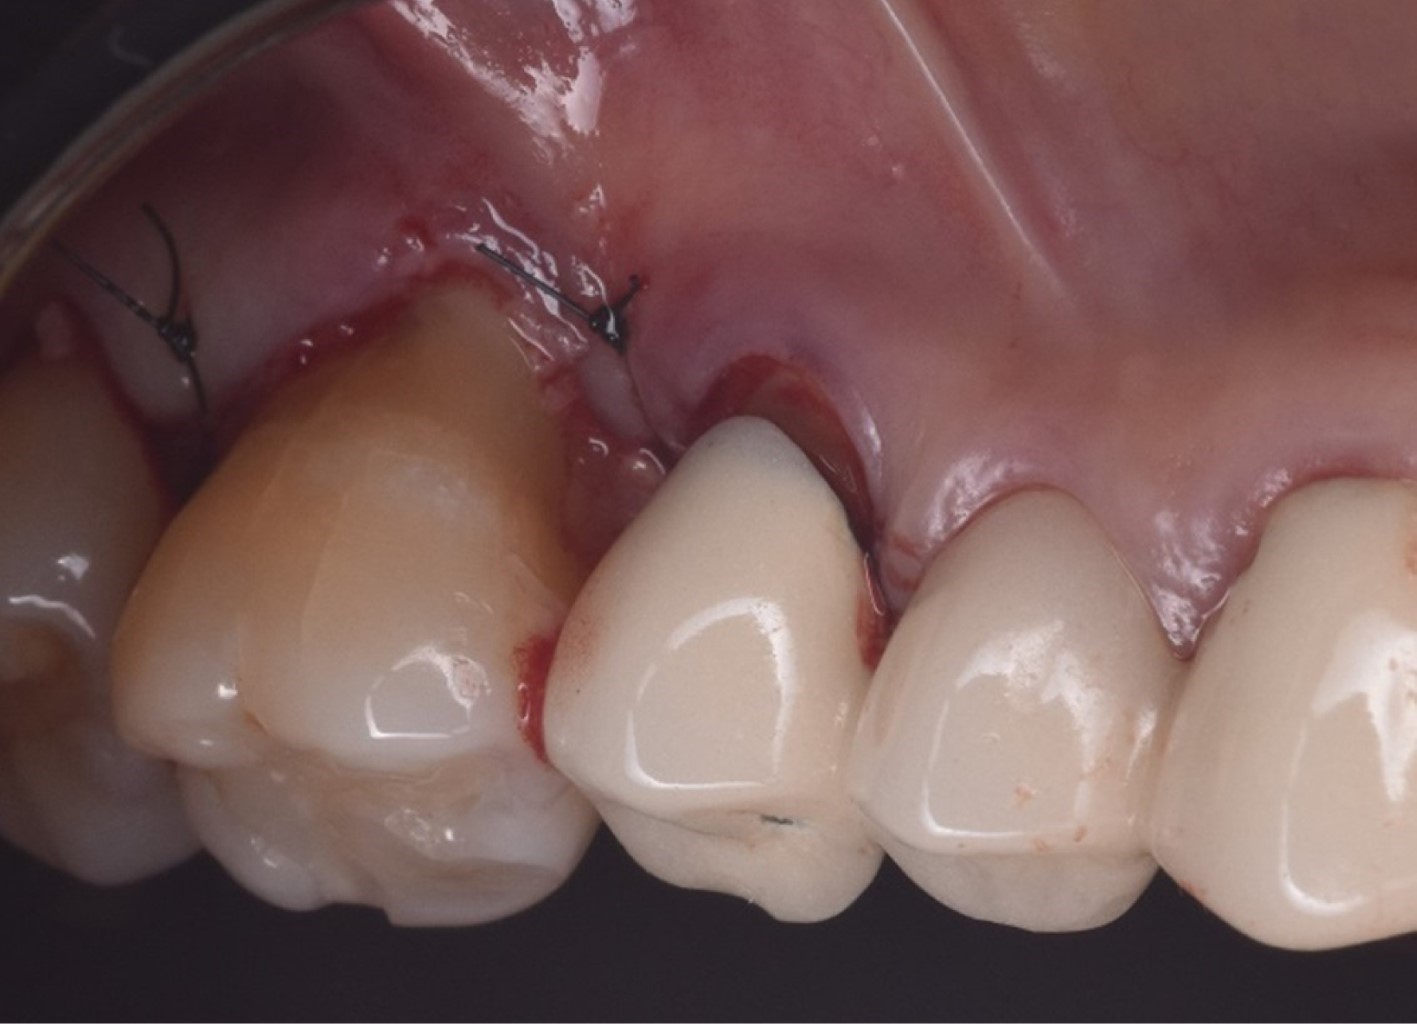

Las proteínas derivadas del esmalte (Emdogain®) se obtienen por medio de la odontogénesis en el periodo de yema de la dentadura porcina; la proteína principal es la amelogenina que presenta una biocompatibilidad con las proteínas del esmalte humano. Los cultivos in vitro han demostrado que Emdogain® al ser agregado a los fibroblastos causa una mejora en la producción de proteínas y colágeno, mineralización y proporciona condiciones favorables a la matriz, proliferación celular, migración, diferenciación y síntesis (Figuras 1, 2, 3, 4, 5 y 6). La capacidad osteogénica se relaciona de manera directa con las proteínas que contiene y esto produce una capacidad osteoinductiva y puede contener factor de crecimiento transformante beta y proteína morfogénica ósea (BMP, por sus siglas en inglés) aunque en menor cantidad.10

Figura 1

Figura 2

Figura 3

Figura 4

Figura 5

Figura 6